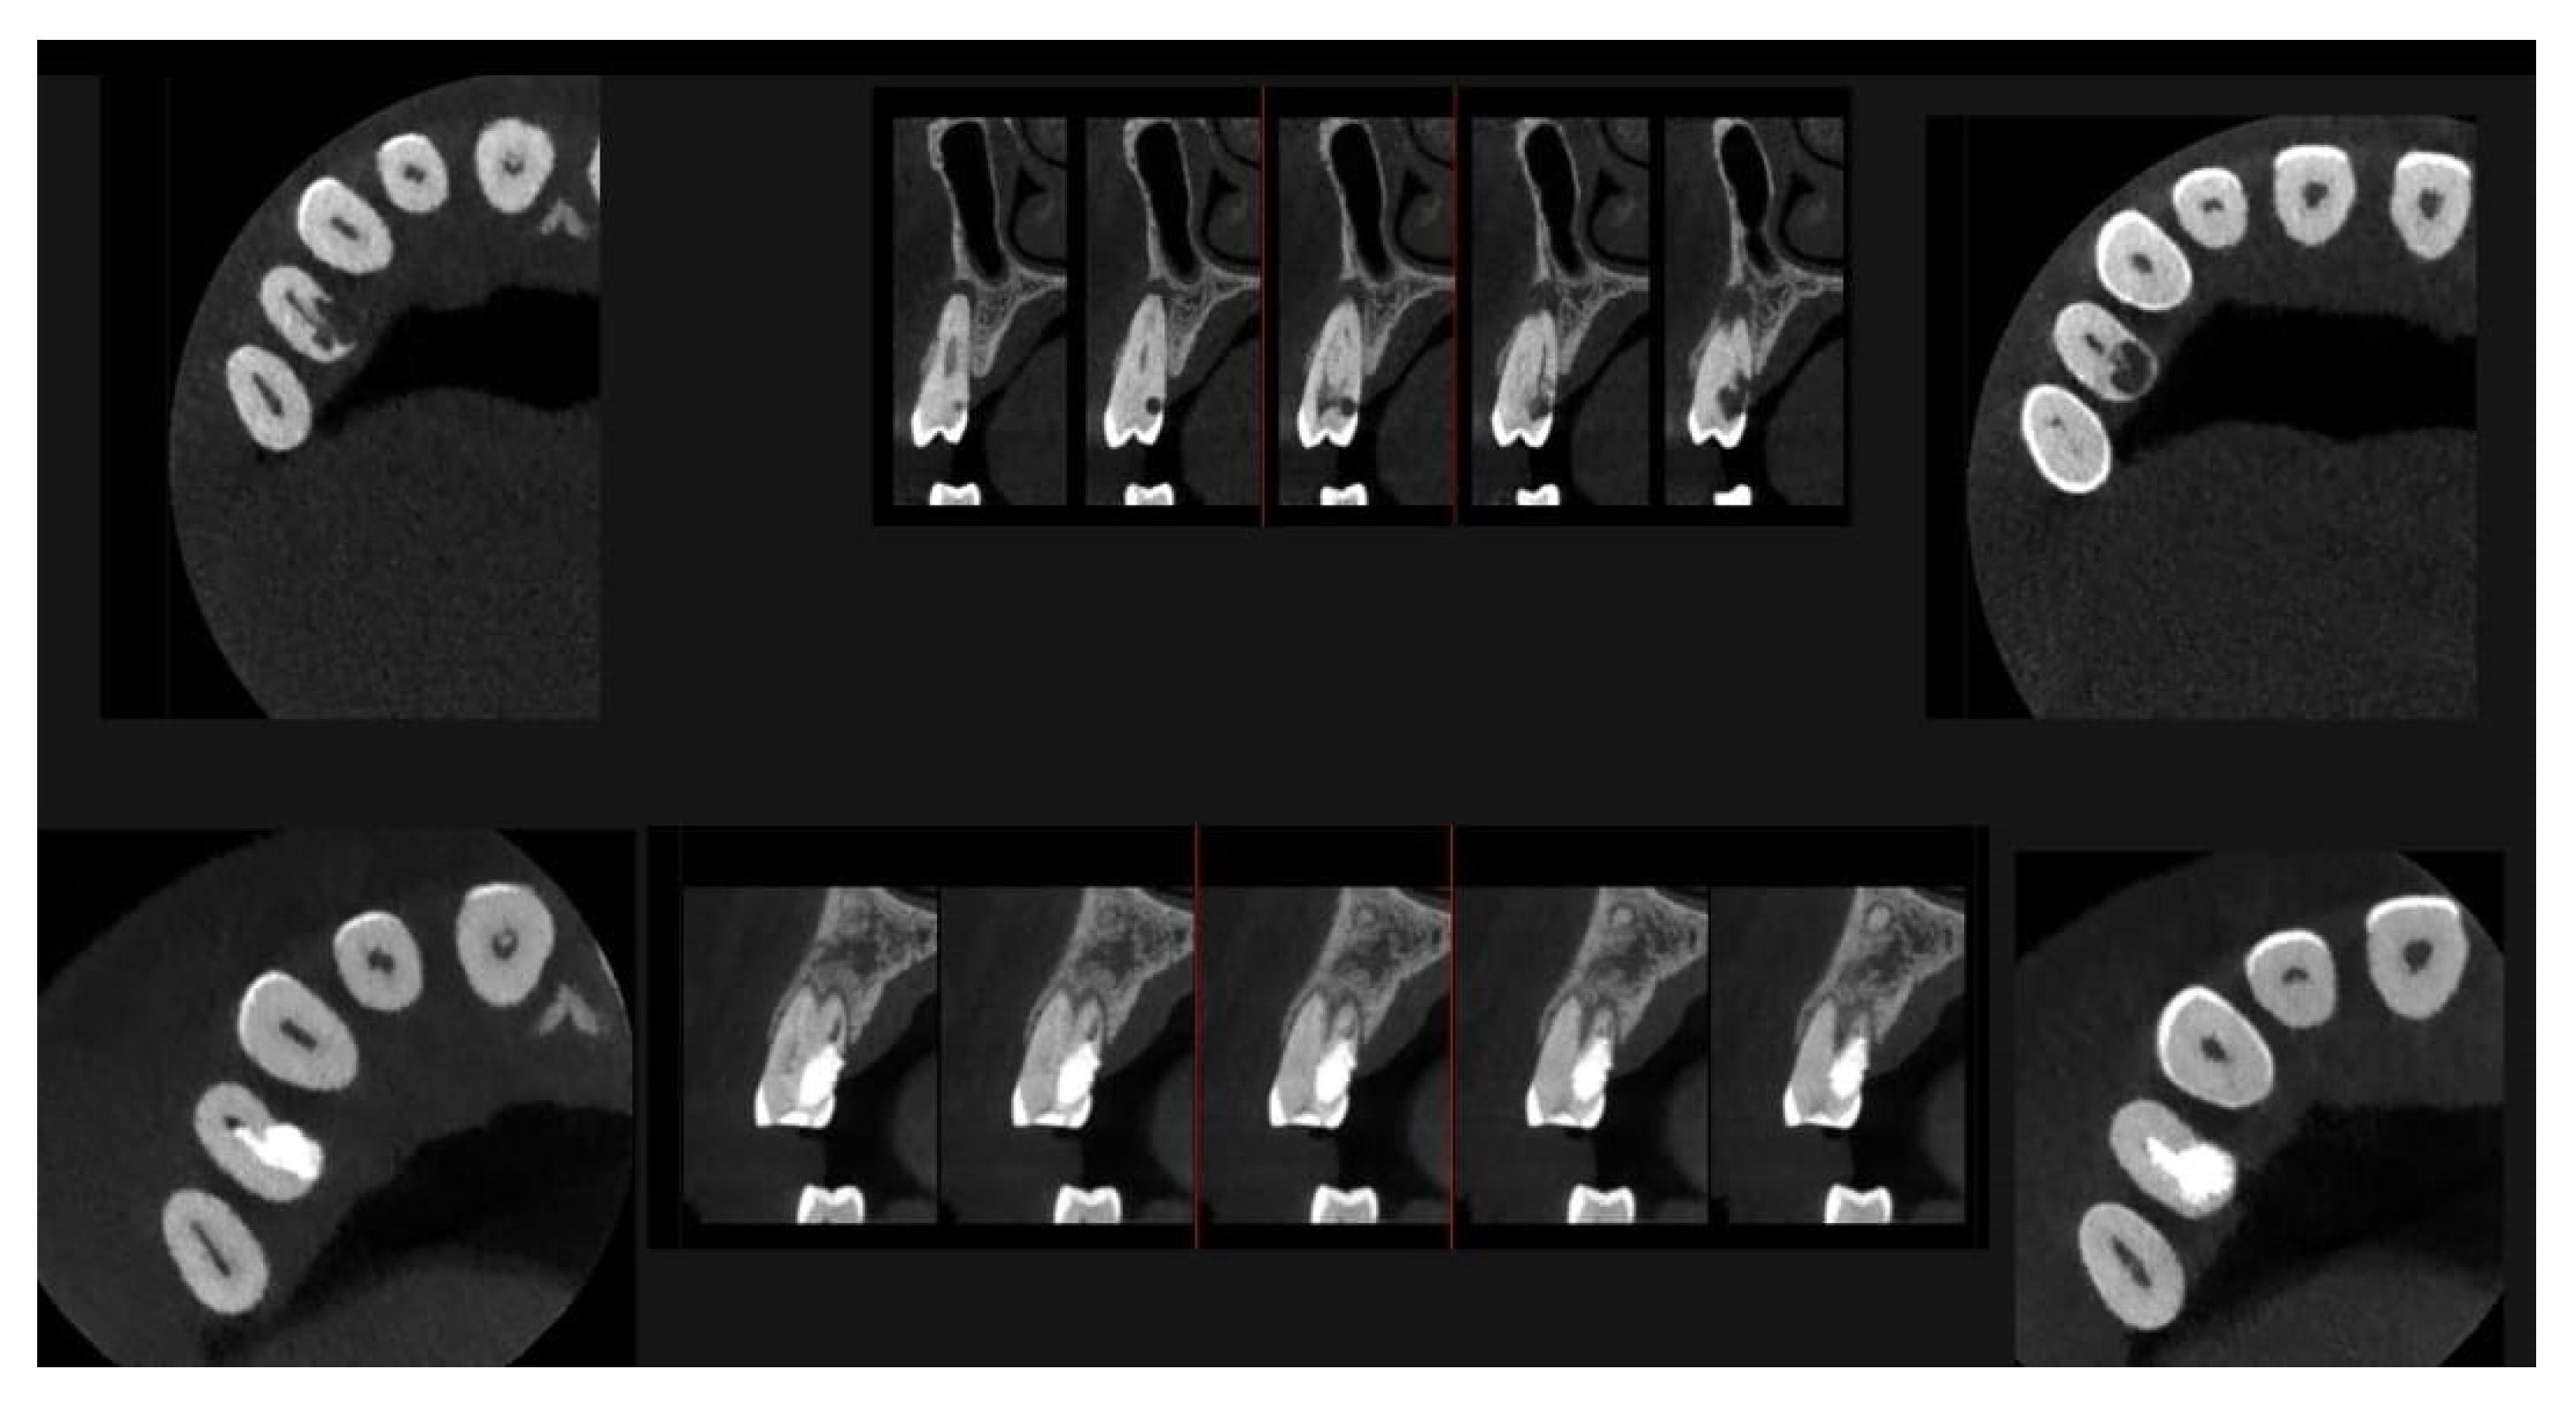

Cross-section CBCT images of tooth 1.4 after six months of healing. (A–I) Sequential scrolling of EPL healing.

Figure 12.

Pano-rex and cross-sectional CBCT images of tooth 1.4 after six months of healing. (A,B) Sequential scrolling of tooth 1.4 after six months of healing. The colored lines crossing the images represent the orthogonal planes (axial, coronal, and sagittal) in the multiplanar reconstruction. Their correct use and orientation allow for an accurate identification of the extent of the lesions in all spatial planes and a detailed analysis of the endodontic anatomy. The green and red letters are the coordinates of the image: A: anterior, R: right, B: bottom, T: Top.

Figure 13.

An intermediate follow-up CBCT scan at 6 months was performed to accurately assess the response to treatment in light of both the extent of the lesion and the patient’s systemic comorbidities (Figure 10, Figure 11, Figure 12, Figure 13 and Figure 14).